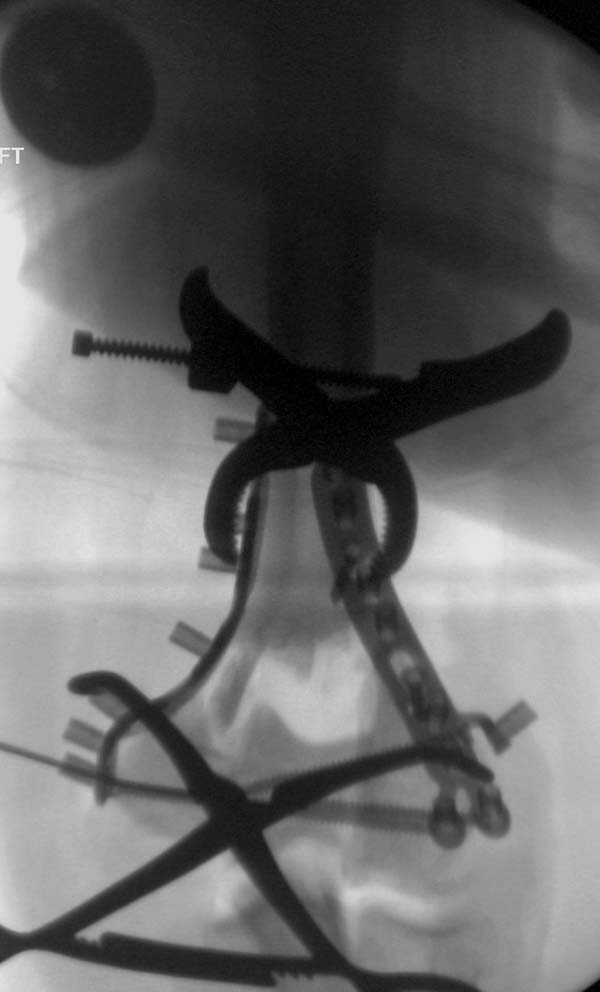

Примеры: первому более 15 лет фиксирован шурупом и tension band

technique, а второй перелом открытый больной 80 лет, после наружного

фиксатора в первом этапе и окончательная фиксация вторично. Третьий раз

внесуставная остеотомия...

Имя     : 2-3 Distal Humerus exfix lat 2.jpg

Тип     : image/jpeg

Размер  : 43897 байтов

Описание: отсутствует

Url     : http://weborto.net:8080/pipermail/ortho/attachments/20130604/c45a379f/attachment-0022.jpg

-----------   -----------

Вложение не в текстовом формате было извлечено&hellip;

Имя     : 2-4 Distal Humerus exfix ap.jpg

Размер  : 46465 байтов

Url     : http://weborto.net:8080/pipermail/ortho/attachments/20130604/c45a379f/attachment-0023.jpg